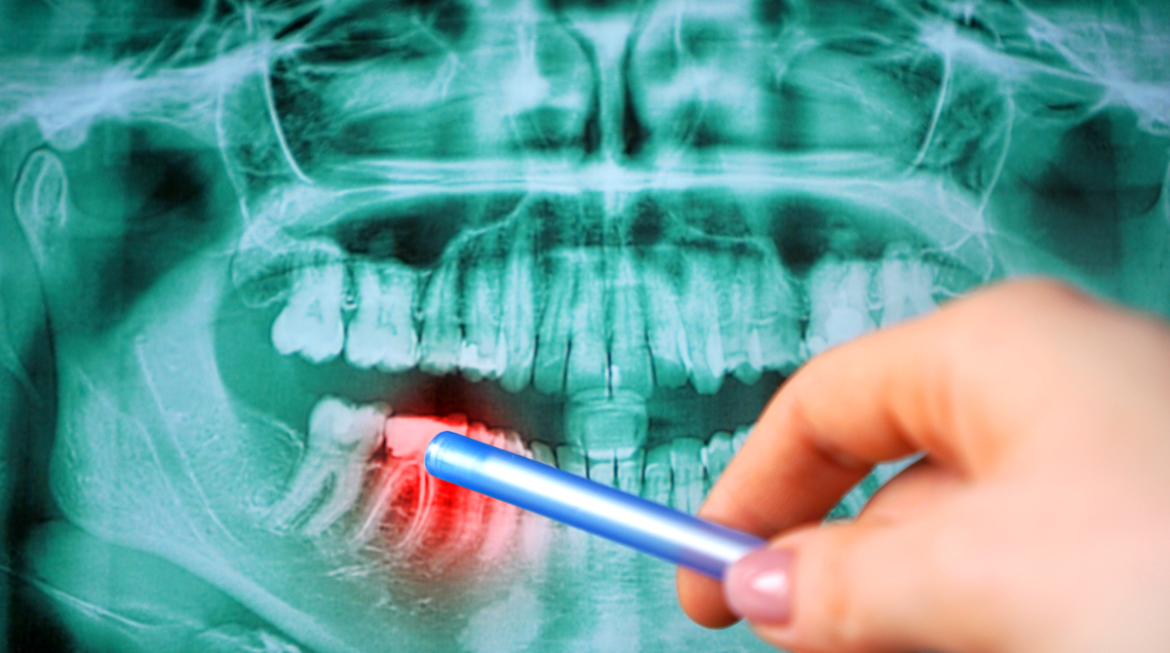

How to Determine if Your Teeth are Too Far Gone to Be Saved

When you have teeth that are damaged it can be difficult to decide on the best course of treatment. In some situations, it is worth getting extensive dental work completed in order to save a tooth or multiple teeth. In other situations, it may not be possible to save the damaged teeth. In order to determine if your teeth are too far gone to be saved, you need to look at how many of your teeth are impacted by the damage, consider the type and scope of the damage, and talk through the options with us at Ministry of Smile, …